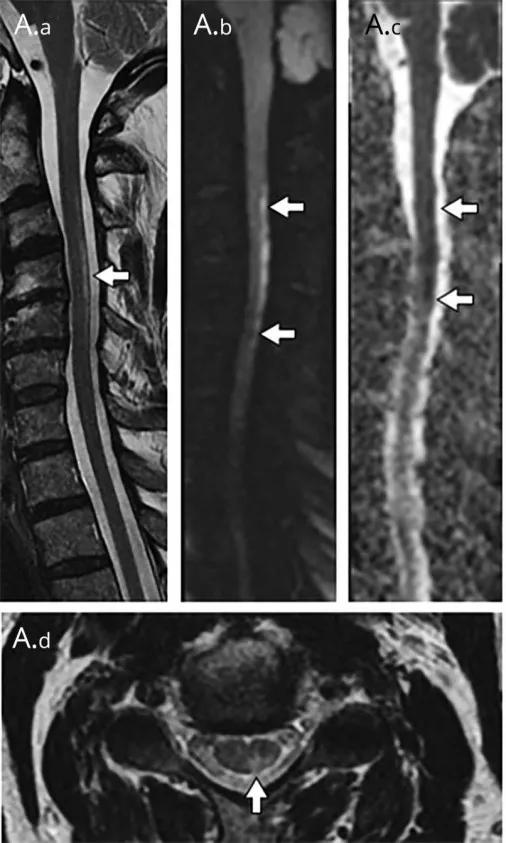

多发性硬化(Multiple sclerosis,MS)亦是一种严重的中枢神经系统自身免疫脱髓鞘病变,免疫球蛋白分泌 B 细胞和浆细胞的克隆性扩增,可使 CSF 中出现寡克隆带特征。

MRI:

脊髓:颈髓较常受累,病灶 T2WI 呈高信号,T1WI 呈稍低信号,轴位常分布于前索、侧索或者后索,长轴 ≤ 2 个连续阶段椎体,急性期呈斑片状、结节状或环形强化。

病灶位于侧索、长度小于3个椎体节段